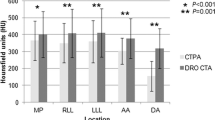

A comprehensive overview of whole lung PBV attenuation values is displayed in Fig. 3. For all resolution settings, we found no significant difference between PBV values of protocols A and B. All other pairwise protocol-comparisons revealed significant differences between PBV values, with PBV values decreasing from protocol A to protocol D (Tables 2 and 3, Fig. 3).

To our knowledge, this is the first study to evaluate the influence of CM injection protocols on absolute PBV values. Our findings indicate that out of IDR, total CM volume and iodine load, a high IDR might be the key factor to obtain higher PBV values: at standard resolution settings, protocol A and B (both high-IDR protocols at 1.75 gI/s) showed no significant differences in PBV at different CM volumes and total iodine loads. On the other hand, when comparing protocols B and C (both with equal CM volume and iodine load), the high-IDR protocol B resulted in significantly higher overall PBV values (30.8 vs. 23.7). However, higher absolute PBV values did not generally translate into superior subjective image quality of iodine maps, as protocols A, B and C received similar subjective image quality ratings. Consequently, apart from high pulmonary parenchymal enhancement expressed by high PBV values, also the ratio of contrast uptake to resulting artefacts has to be taken into account.